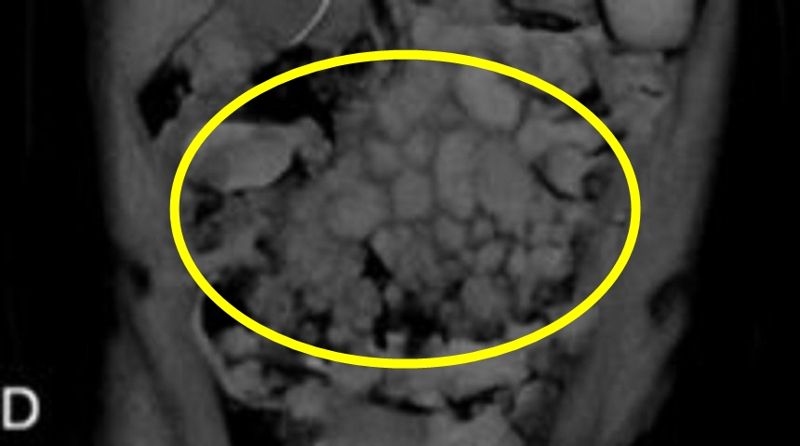

혈액암을 진단받은 20대 여성이 회충에 감염된 후 사망한 사례가 보고됐다. 사진은 장 주변 림프절 비대, 장중첩 발생한 사례 여성 복부CT/사진=큐레우스

멕시코 호세 엘레우테리오 곤살레스대병원 내과 의료진에 따르면 23세 여성이 빈혈과 복통 등 전신 증상을 호소하며 입원해 정밀 검사를 받았다. 검사 결과 해당 여성은 버킷림프종을 확진 받았다.

이는 비호지킨 림프종에 속하며 진행 속도가 매우 빠른 공격형 림프종으로 분류된다. 림프종은 림프구가 악성 종양으로 변이된 것으로, 골수나 혈관, 복부 장기 등에 침투해 두통이나 구토, 복부 비대 등을 유발하는 경우가 잦다.